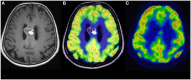

Advances in metabolic imaging techniques have allowed for more precise characterization of gliomas, particularly as it relates to tumor recurrence or pseudoprogression. Furthermore, the emerging field of radiogenomics where radiographic features are systemically correlated with molecular markers has the potential to achieve the holy grail of neuro-oncologic neuro-radiology, namely molecular diagnosis without requiring tissue specimens. In this section, we will review the utility of metabolic imaging and discuss the current state of the art related to the radiogenomics of glioblastoma.